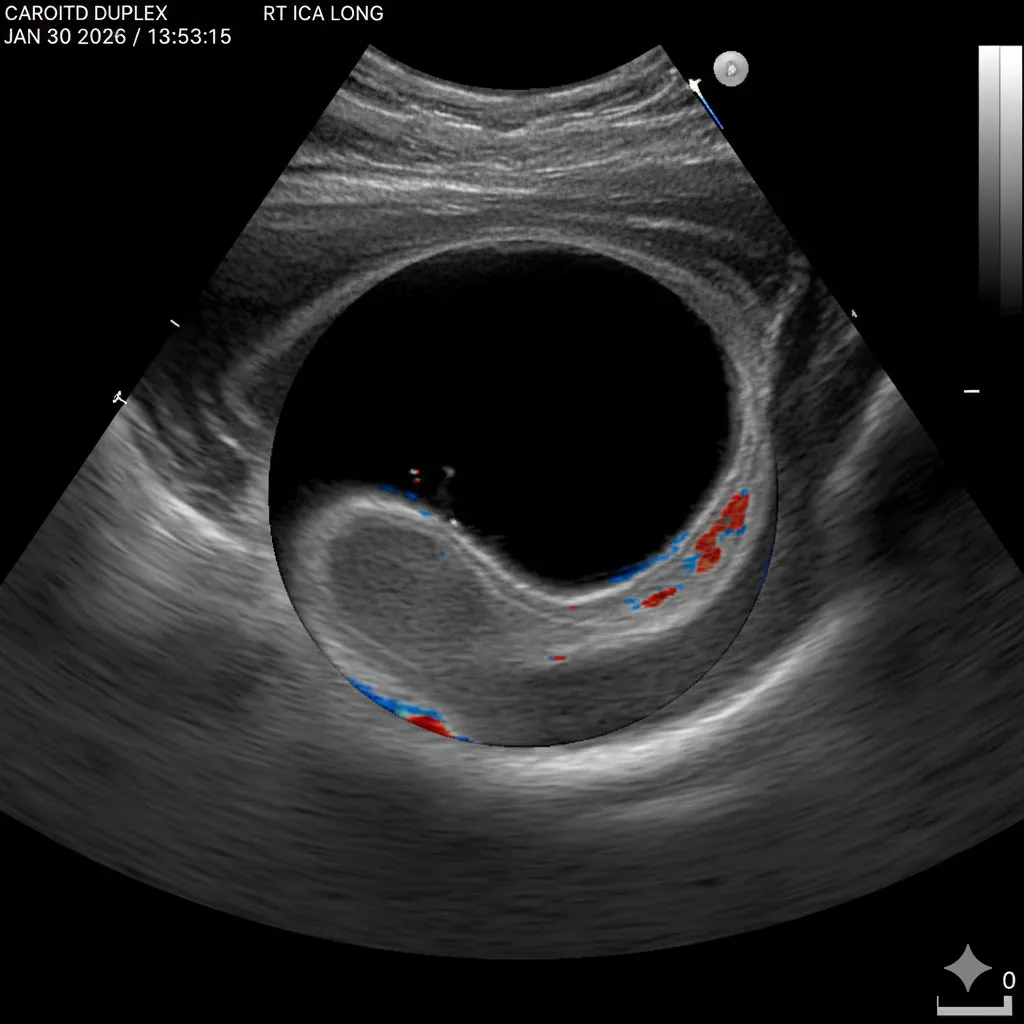

A carotid duplex ultrasound is a noninvasive test that looks at:

plaque in the carotid artery walls

how narrowed the artery is (stenosis)

blood flow speed and patterns

It does not diagnose “TIA” by itself — it helps identify a possible cause and guide next steps.